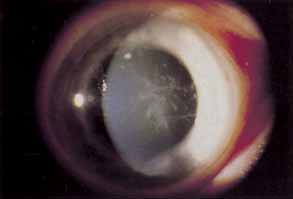

SUPERFICIAL NEOVASCULARIZATION

Superficial corneal neovascularization is a response to persistent hypoxia secondary to contact lens wear (Fig. 3).9,101–103 Rigid lenses rarely develop limbal hyperemia greater than normal controls. Daily wear–lens patients will often show an apparent increase in limbal vascularization, which actually represents limbal capillary dilation and rarely progresses to frank neovascularization. Extended-wear soft contact lens wearers most often exhibit significant limbal new vessel growth. Topical nonsteroidal antiinflammatory agents may suppress neovascularization, but their use has not become routine.104 Most often treatment consists of changing from extended to daily wear schedules, fitting with higher dK or thinner lenses or fitting with a looser soft lens. The use of soft extended wear lenses after penetrating keratoplasty is particularly risky because of the rapid neovascular response observed.105

Fig. 3 Severe superficial corneal neovascularization.